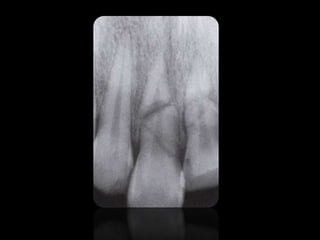

QUISTES

REABSORCIONES ÓSEAS